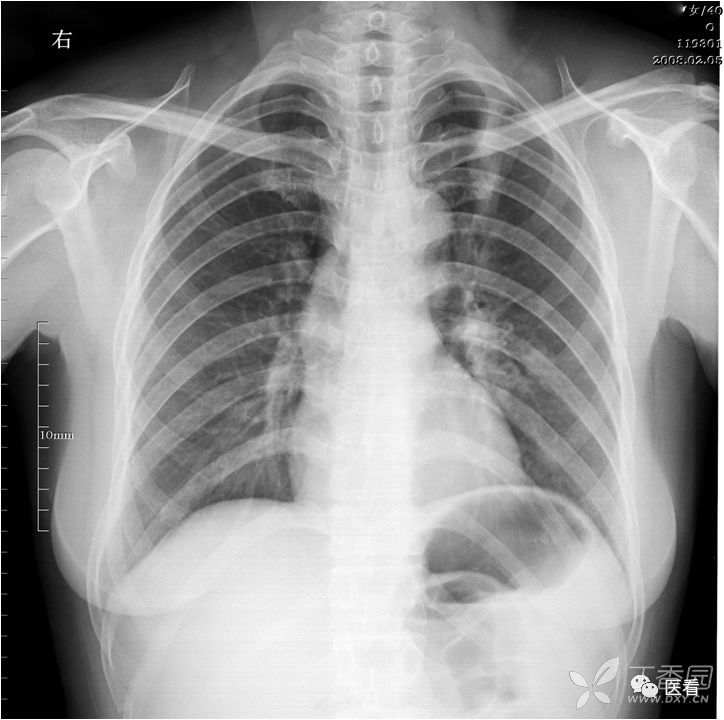

火眼金睛辨真伪:申请单病情摘要:男,44岁,胸痛两天,查体无特殊。

看上去是心脏普遍增大。细心观察,右肺门及右下肺动脉影被掩入增大的心影内(蓝箭头)

本例为食管癌手术后,服用钡餐后,显示实际为胸腔胃(红箭)形成的假象。

真正的心脏增大,肺门及下肺动脉影被向外推移(蓝箭头),在心影外